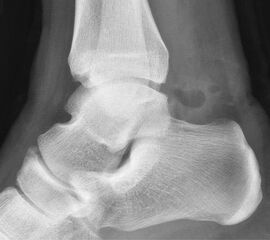

• Röntgenbild des OSG in 2 Ebenen.

Reseziertes Os trigonum sowie prä- und postoperatives seitliches Röntgenbild nach arthroskopischer Entfernung eines Os trigonum.